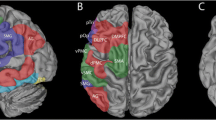

a For representative left (upper) and right (lower) language dominant subjects, activation maps for each fMRI task show voxels that have more activation during the active blocks compared to the control blocks. Maps are thresholded at z-statistics of 3.5 and 3.0 for the left- and right-dominant subjects, respectively. Graphs show how the laterality index (LI) for each subject varies as a function of increasing z-statistic threshold for each of the 4 tasks and the full or partial functional masks. b Relationship between z-statistics and percentile subject activation. At each percentile activation, blue circles plot the range of z-statistics observed across the population of 59 subjects. For the population, the fitted black curve and shaded gray region show how the average +/− SD z-statistic varies as a function of percentiles of subject activation. c For the functional mask, graphs show how the average and standard error (shaded region) of the population laterality index vary as a function of percentile thresholds for each of the 4 tasks and the full or partial masks. d The 2 patient subgroups (patients with masses/AVMs and patients with epilepsy), show a similar pattern of change in the average laterality index as a function of percentile thresholds when compared to each other and the entire population (c). AL anterior-left brain orientation, AR anterior-right brain orientation, AT auditory tones, PL passive listening, MR mental rhyming, VG verb generation

To facilitate population-level comparisons, we computed LIs as a function of percentile thresholds of each subject’s voxel-wise activation across all tasks. Using percentiles allowed us to compare across tasks and subjects without assumptions about the underlying distribution of activations in individual subjects. Figure 2b shows the range of z-statistics across the 59 subjects corresponding to these percentiles of subject activation. This plot highlights (1) the variability in individual subject activations at each percentile and (2) the exponential shape of the overall relationship between z-statistics and percentiles of activation. Subsequent population-level analyses expressed activations as percentiles of individual subject activation on a log axis.

Figure 2c shows results of a population-level analysis analogous to the subject-level analysis in Fig. 2a. For the full functional mask and each subcomponent, for each task we plotted the average and standard error (shaded region) of the LIs across the population at each percentile threshold. Figure 2d shows results of the same population-level analysis applied separately to the subgroup of patients whose primary diagnosis was AVM or mass and the subgroup whose primary diagnosis was epilepsy. For the population as a whole and for both subgroups, we saw clear differences in language task performance; in particular, at thresholds above the 90th percentile, VG produces greater average laterality indices than MR, with both VG and MR outperforming PL. An analogous population-level plot created using the anatomic masks can be found in Online Resource 3.